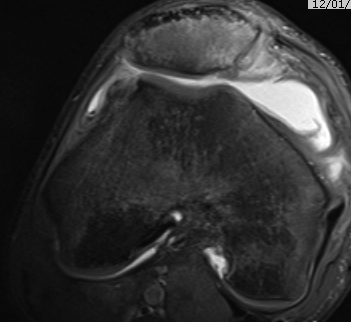

MRI

Demonstrates

- MPFL tear

- cartilage damage

- loose body

Osteochondral fracture (40-50%)

- LFC or medial facet patella

- patient will have haemarthrosis